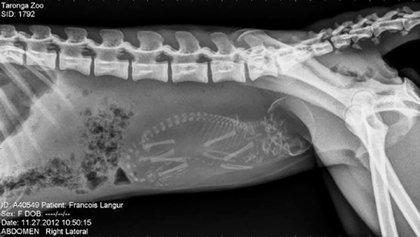

哈~這其實是動物懷孕的照片啦!美國《boredpanda》網站最近整理了一系列懷孕動物的X光照,從最常被人類飼養的貓、狗,乃至於蝙蝠、浣熊等都有,雖然小動物的誕生應該是可愛而溫馨,不過單看這些滿肚骨骸的X光照,還是覺得有點驚悚和詭異啊!

佛朗索瓦葉猴